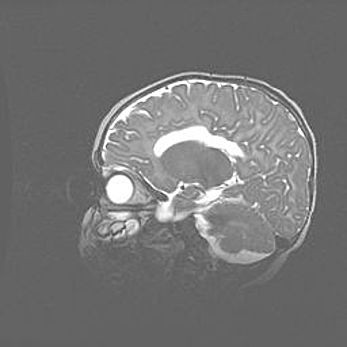

Аномалия Денди-Уокера. Признаки гипоплазии мозолистого тела.

Возраст: 5 месяцев 3 дня

Вес: 5550 г

Пол: мужской

Окружность головы: 39 см

Срок гестации: 40 недель

Аномалия Денди-Уокера – это порок развития головного мозга, для которого характерна триада симптомов: гипотрофия или аплазия червя мозжечка и/или полушарий мозжечка, расширение четвёртого желудочка с формированием ликворной кисты задней черепной ямки, гипертензионная гидроцефалия различной степени.

Гипоплазия мозолистого тела относится к дефектам внутриутробного этапа развития мозговой ткани, возникающим в процессе закладки структур головного мозга, что происходит на начальных этапах развития эмбриона.